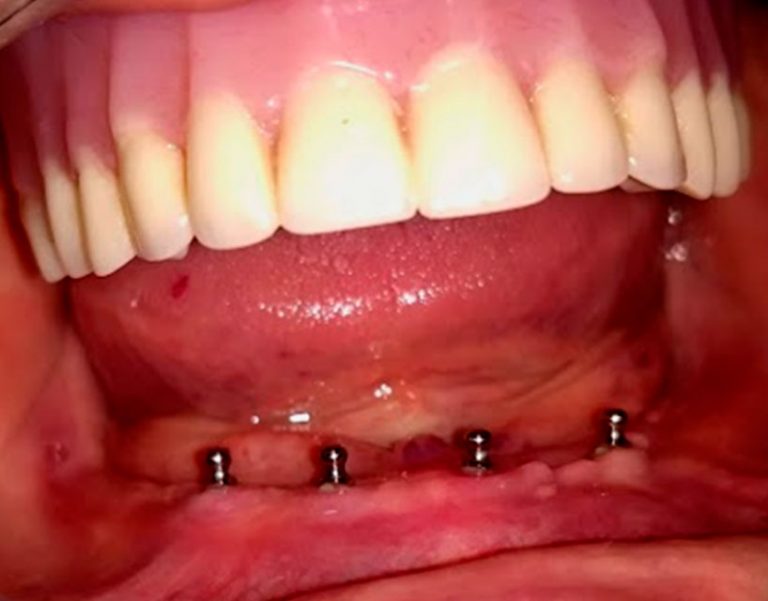

Protesis total sobre implantes